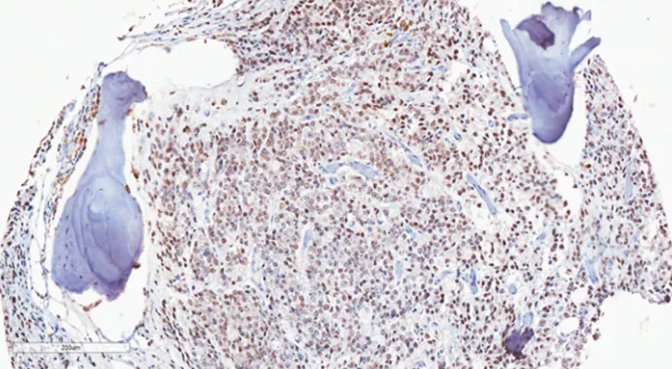

使用抗 AR-V7兔单克隆抗体(克隆 RM7)对福尔马林固定和石蜡包埋骨转移前列腺癌的免疫组化染色。经临床验证 ARv7 呈阳性。图片由美国华盛顿大学的Stephen Plymate 博士提供。